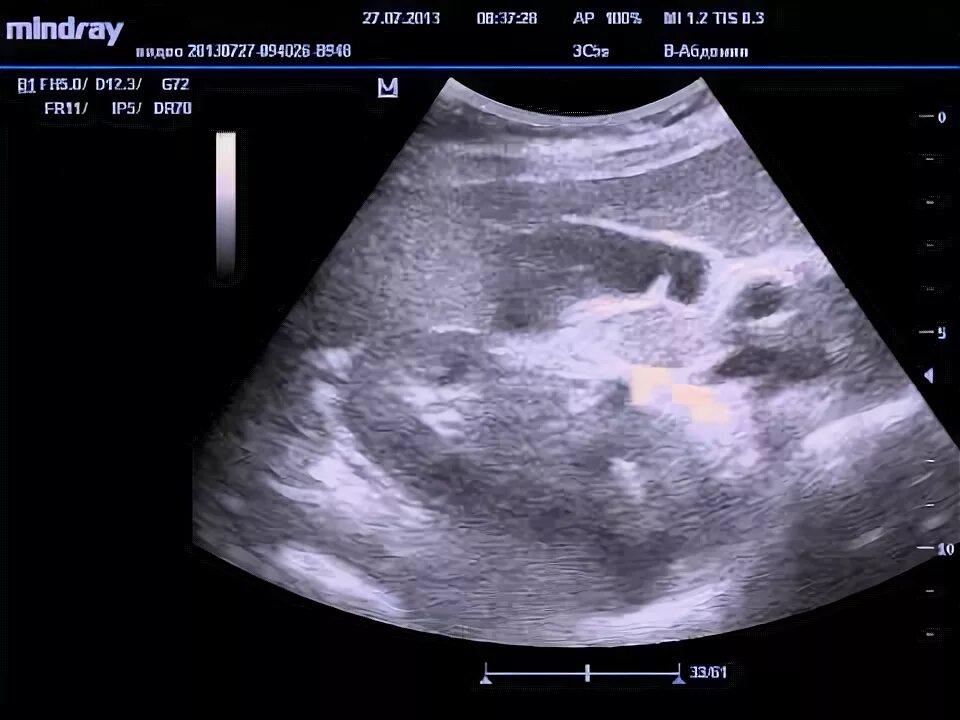

Перетяжка желчного пузыря симптомы